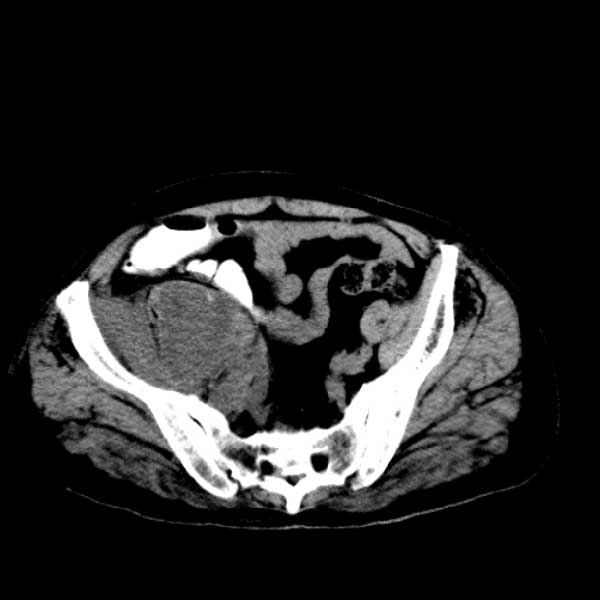

标题: CT13513:男 71 腹部疼痛20余天,近几天高热就诊,骨窗未见异 [打印本页]

标题: CT13513:男 71 腹部疼痛20余天,近几天高热就诊,骨窗未见异

考虑感染性病变可能性大,起源于阑尾?

感染,脓肿形成

考虑为化脓性阑尾炎.脓肿形成.及多肌肉累及.

考虑右侧腰大肌脓肿,向右髂窝、右腹股沟流注。

支持化脓性阑尾炎伴右髂窝脓肿、腰大肌腰方肌脓肿形成。

考虑腹腔及盆腔化脓性炎症,累及右侧髋关节及腹股沟区.

首先考虑化脓性阑尾炎伴腰大肌、腰方肌脓肿,不除外回盲部结核。

回盲部癌待排除。

患者肠镜检查考虑结肠癌,病理证实

患者肠镜检查考虑结肠癌,病理证实。肺部ct可见多发结节,考虑转移